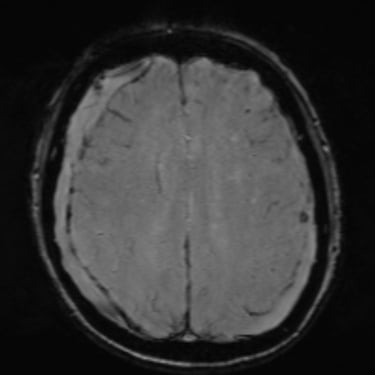

Hematoma Subdural Crónico | Diagnóstico por Resonancia Magnética

El hematoma subdural crónico es una acumulación lenta de sangre entre la duramadre y la superficie cerebral, generalmente secundaria a traumatismos leves en pacientes mayores o anticoagulados. Sus síntomas pueden incluir cefalea persistente, debilidad, alteraciones del lenguaje o cambios en el comportamiento. La resonancia magnética cerebral permite identificar con precisión la extensión y la antigüedad del sangrado, diferenciándolo de otras lesiones intracraneales. Este estudio es esencial para planificar el tratamiento, que puede requerir drenaje quirúrgico mediante trepanación o craneotomía mínima, permitiendo la recuperación neurológica progresiva y reduciendo el riesgo de recurrencia.